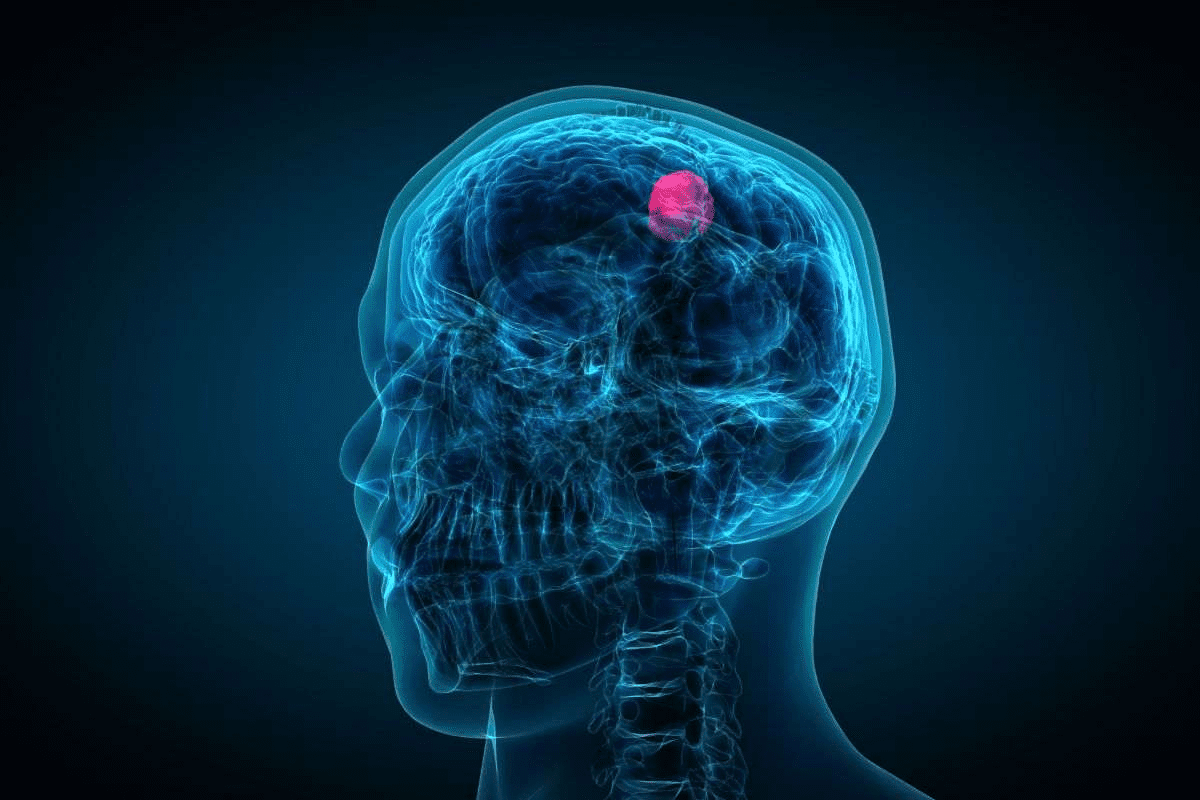

What is Colon Cancer?

Colon cancer happens when cells in the colon or rectum grow too much. The American Cancer Society says this can cause tumors. These tumors can harm nearby tissues and organs.

The Development Process of Colon Cancer

It’s key to know how colon cancer starts to catch it early. Colon cancer usually begins with harmless polyps in the colon. These can turn into cancer over time.

From Polyps to Cancer

The change from polyps to cancer is slow. Not all polyps turn into cancer, but the risk goes up with size and number. The American Cancer Society says colon cancer starts as harmless polyps that can turn bad later.

Genetic changes play a big role in this process. These changes affect how cells grow and divide. They can come from genes or the environment.